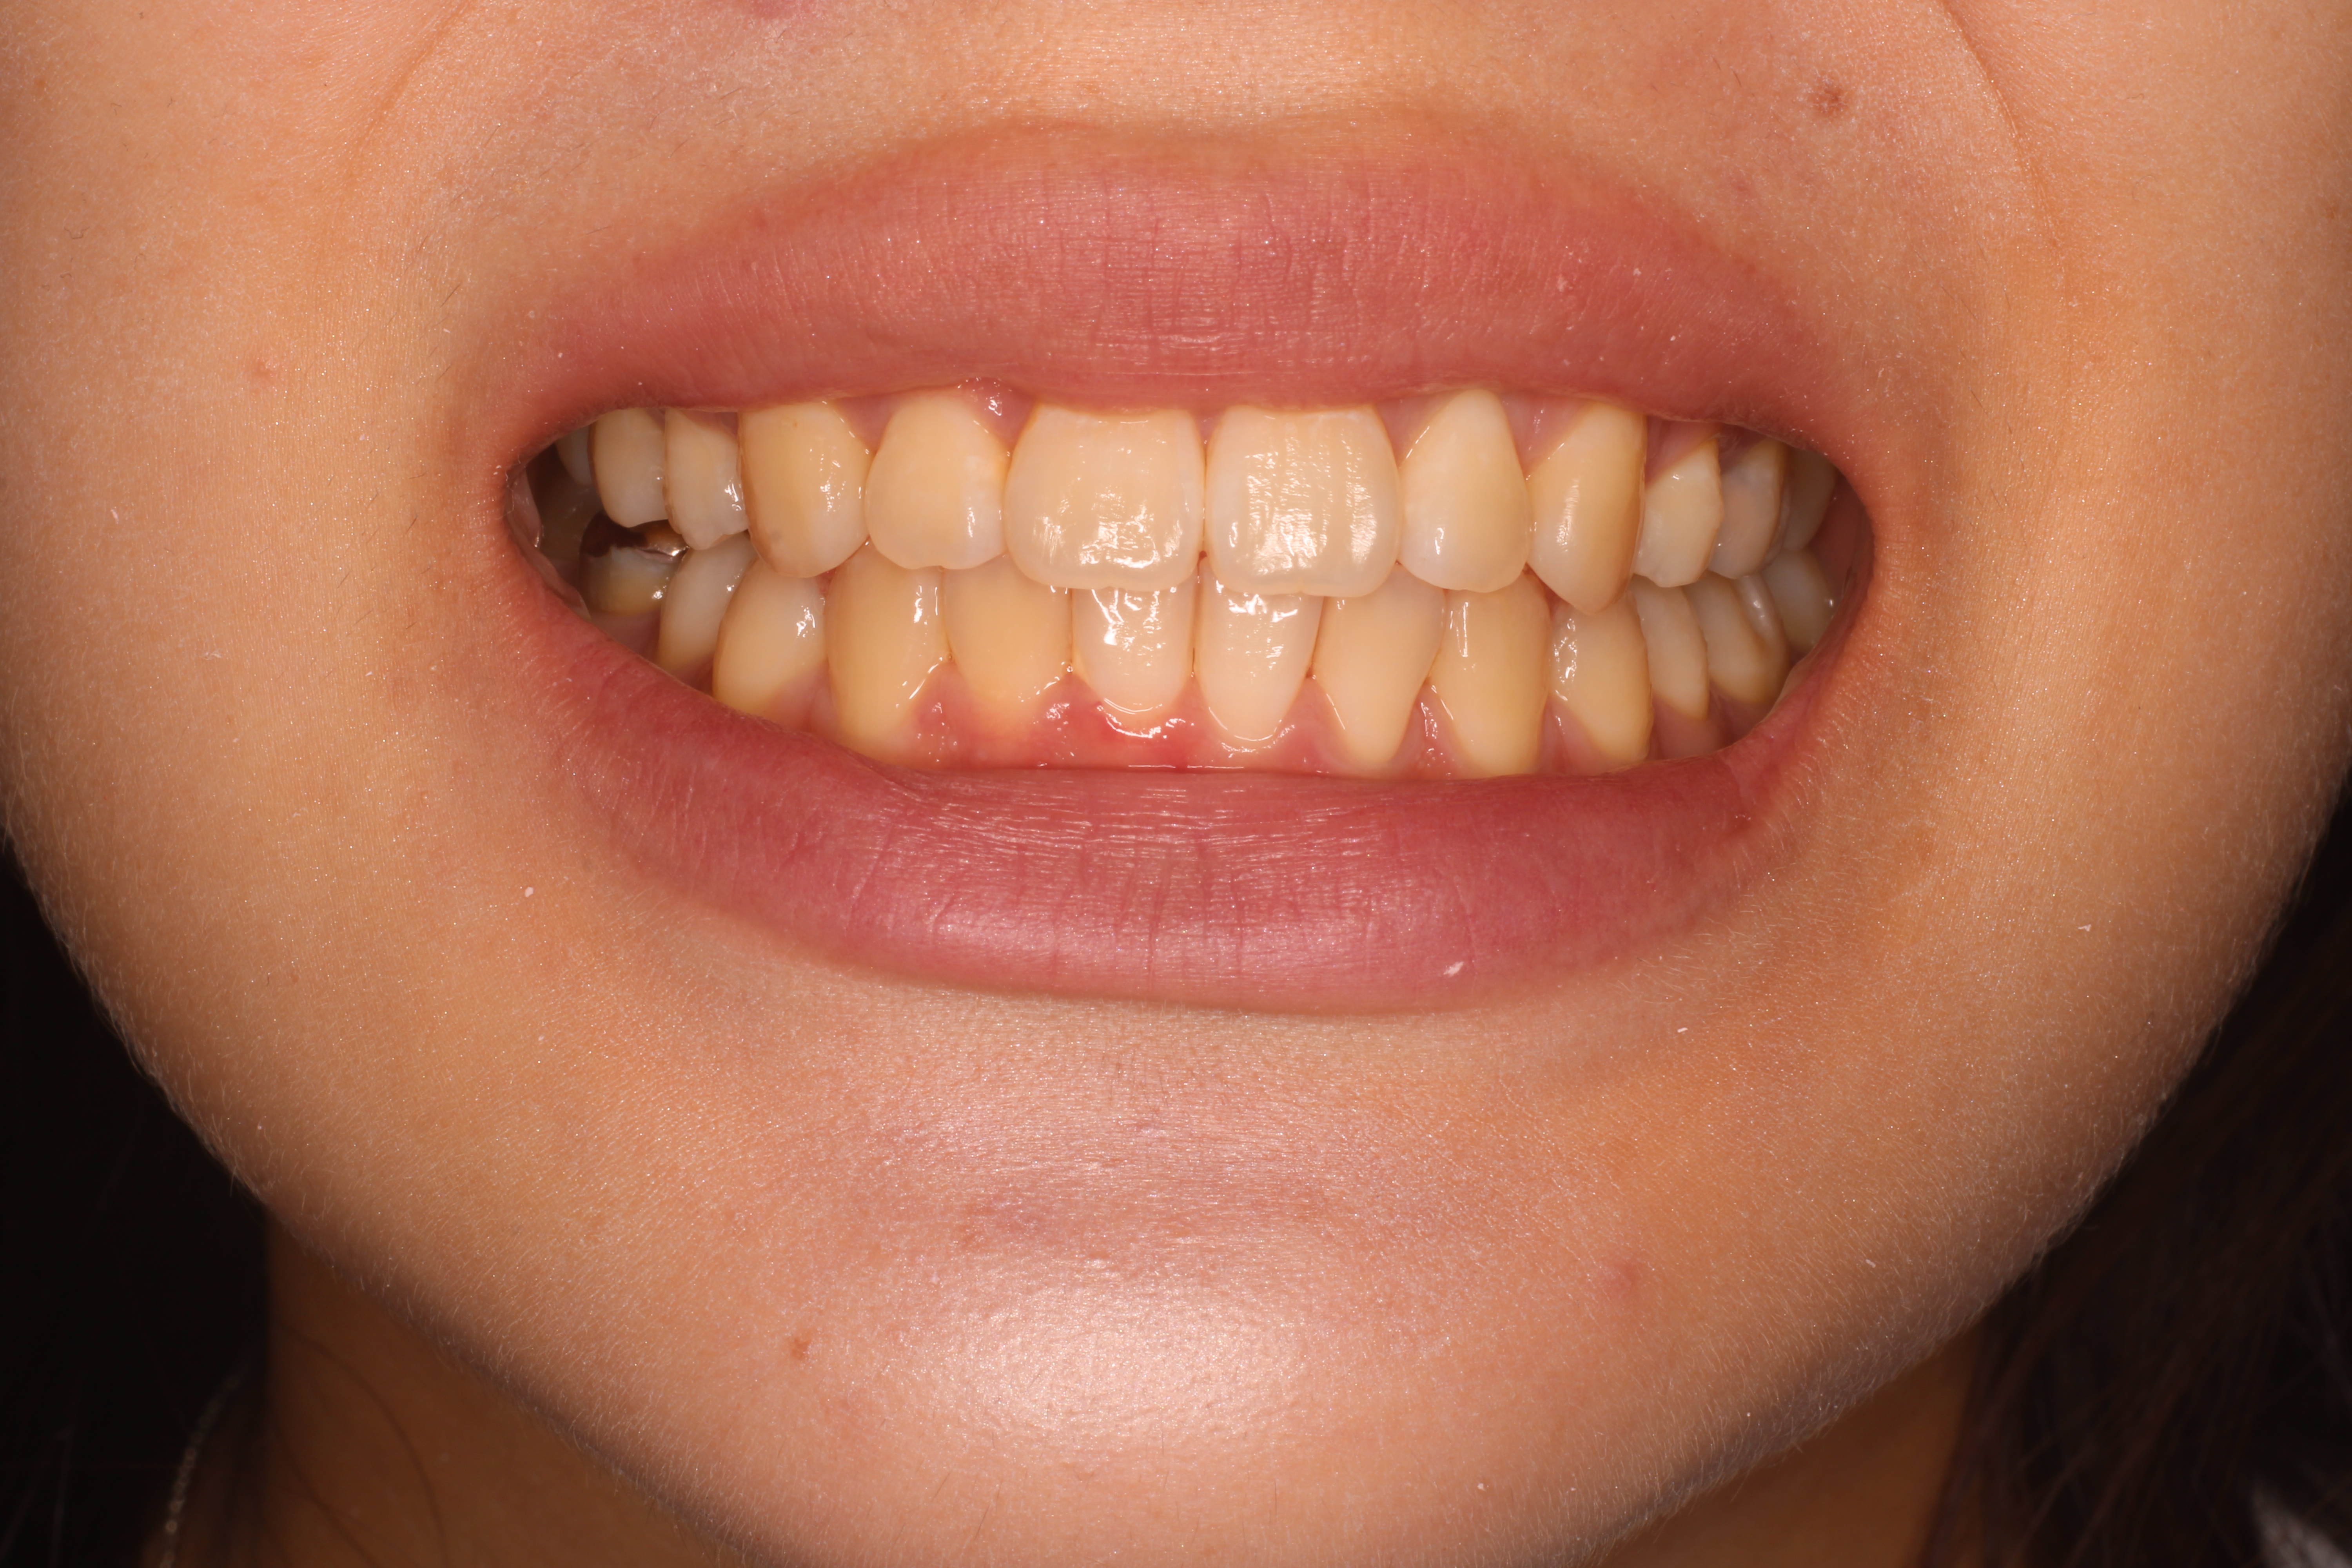

術前術後BEFORE AFTER

術前

BEFORE

AFTER